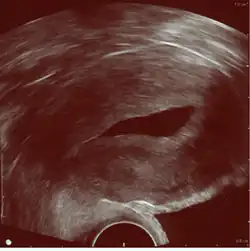

![]() Left hydrosalpinx on gynecologic ultrasonography | |

Gynecologic ultrasonography or gynecologic sonography refers to the application of medical ultrasonography to the female pelvic organs (specifically the uterus, the ovaries, and the fallopian tubes) as well as the bladder, the adnexa, and the recto-uterine pouch. The procedure may lead to other medically relevant findings in the pelvis.This technique is useful to detect myomas or mullerian malformations.